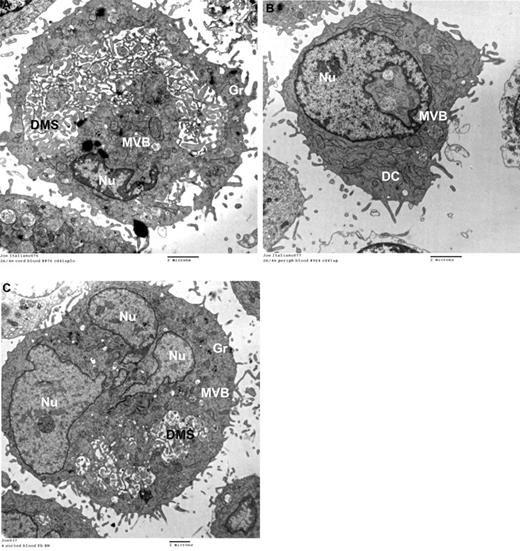

To confirm that the lower CD42b levels indeed reflected less-mature MKs, we also evaluated the ultrastructure of rapamycin-treated CB-MKs by electron microscopy. In this study, 81% of control MKs (DMSO-treated; n = 90) exhibited a DMS (Figure 7A), compared with 41% of rapamycin-treated MKs (n = 85). Most rapamycin-treated MKs exhibited scant cytoplasm, few granules, and an absent DMS (Figure 7B).

Ultrastructure and protein-expression levels of GATA-1 and C-MPL in rapamycin-treated versus control CB-MKs. (A) Representative electron photomicrograph of a CB-MK cultured in 0.01% DMSO (controls) exhibiting a large cytoplasm, a large cytoplasm/nucleus (Nu) ratio, abundant granules (Gr), and an open DMS. (B) Ultrastructural characteristics of MKs treated with rapamycin showing a striking reduction in cytoplasm, nearly absent granules, and a lack of DMS. Features of very immature MKs were frequently observed, including multivesicular bodies (MVB) and dense compartments (DC). (C) Under the same experimental setting described in Figure 4, MKs were starved overnight and then stimulated with TPO in the presence or absence of rapamycin (50nM). Pretreatment with rapamycin significantly suppressed phosphorylation of S6K and 4E-BP-1 upon TPO stimulation in CB-MKs. (D) In separate experiments, MKs treated with rapamycin from day 11 until day 14 of culture had significantly lower protein levels of GATA-1 and C-MPL compared with control MKs. Bars reflect the means ± SEM of 3 independent experiments. *P < .05.

Finally, we evaluated the effects of rapamycin at the molecular level. After confirming in signaling studies that pretreatment with rapamycin suppressed the phosphorylation of mTOR targets after TPO stimulation (Figure 7C), we added rapamycin or DMSO to our CB cultures starting on day 11, when the majority of MKs are undergoing terminal maturation. After 3 days of culture, GATA-1 and C-MPL protein levels were substantially lower in rapamycin-treated compared with control MKs (Figure 7D). However, rapamycin did not affect GATA-1 mRNA levels measured 24, 48, and 72 hours after the addition of rapamycin (data not shown), suggesting that mTOR might regulate GATA-1 expression in human MKs at the posttranscriptional level.